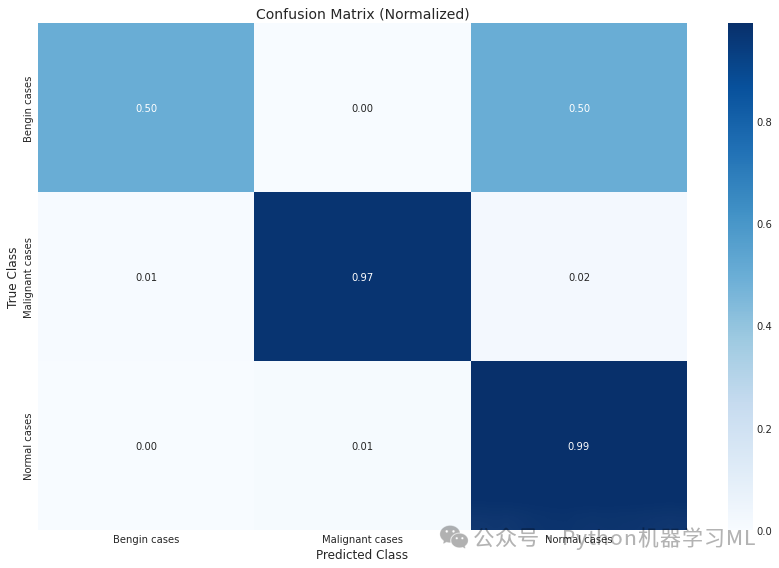

Classification Report:[[ 15 0 15] [ 1 137 3] [ 0 1 103]]Classification Report: precision recall f1-score support 0 0.94 0.50 0.65 30 1 0.99 0.97 0.98 141 2 0.85 0.99 0.92 104 accuracy 0.93 275 macro avg 0.93 0.82 0.85 275weighted avg 0.93 0.93 0.92 275

第二阶段:混淆矩阵可视化

conf_mat_norm = conf_mat.astype('float') / conf_mat.sum(axis=1)[:, np.newaxis] # 计算归一化的混淆矩阵

# Plot normalized confusion matrix

plt.figure(figsize=(12, 8)) # 创建新图形

sns.heatmap(conf_mat_norm, annot=True, fmt='.2f', cmap='Blues',

xticklabels=categories,

yticklabels=categories) # 使用热力图绘制归一化的混淆矩阵

plt.xlabel('Predicted Class') # 设置x轴标签

plt.ylabel('True Class') # 设置y轴标签

plt.title('Confusion Matrix (Normalized)') # 设置标题

plt.tight_layout() # 调整布局

plt.savefig("Confusion Matrix (Normalized)") # 保存图形

plt.show() # 显示图形